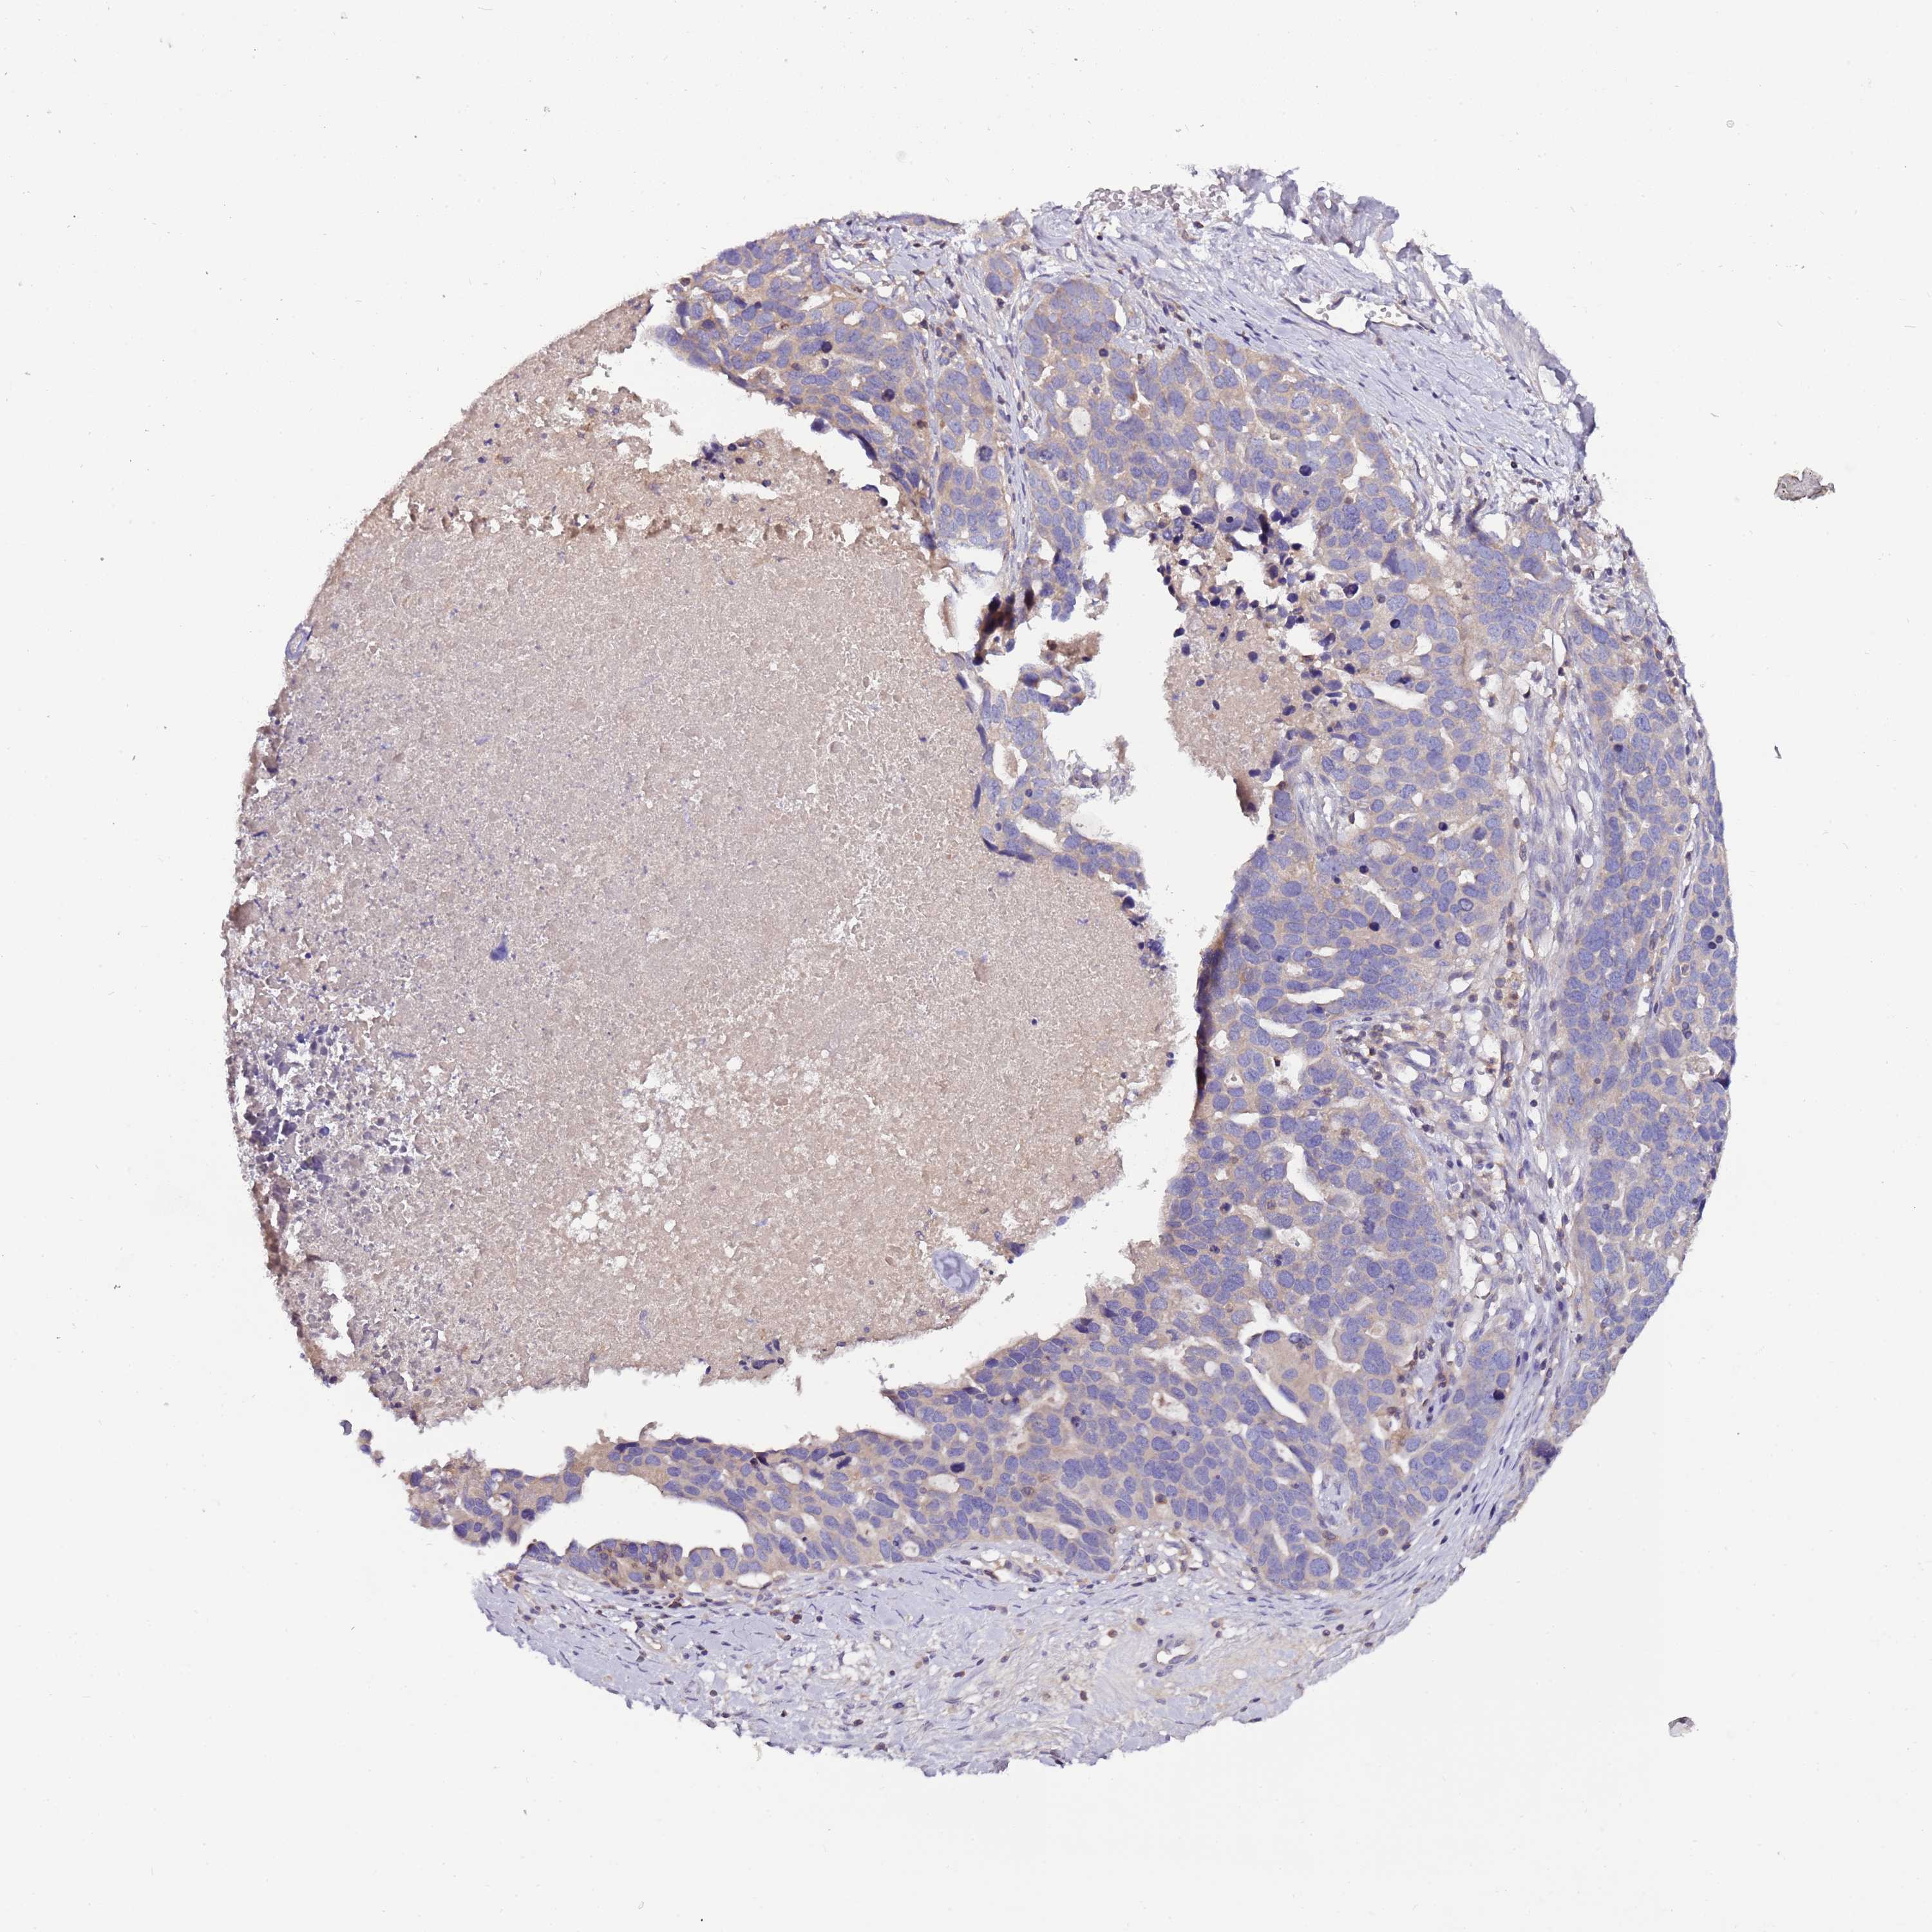

OVARIAN CANCER - Protein expressioni

A mouse-over function shows sample information and annotation data. Click on an image to view it in a full screen mode. Samples can be filtered based on level of antibody staining by selecting one or several of the following categories: high, medium, low and not detected. The assay and annotation is described here.

Note that samples used for immunohistochemistry by the Human Protein Atlas do not correspond to samples in the TCGA dataset.

Antibody stainingi

Antibody staining in the annotated cell types in the current human tissue is reported as not detected, low, medium, or high, based on conventional immunohistochemistry profiling in selected tissues. This score is based on the combination of the staining intensity and fraction of stained cells.

Each image is clickable and will lead to virtual microscopy that enables deeper exploration of all samples and also displays staining intensity scores, fraction scores and subcellular localization as well as patient and tissue information for each sample.

Antibody HPA048615

Staining

High

Medium

Low

Not detected

Intensity

Strong

Moderate

Weak

Negative

Quantity

>75%

75%-25%

<25%

None

Location

Nuclear

Cytoplasmic/membranous

Cytoplasmic/membranous,nuclear

Cystadenocarcinoma, serous, NOS

Carcinoma, NOS

Cystadenocarcinoma, mucinous, NOS

Carcinoma, endometroid